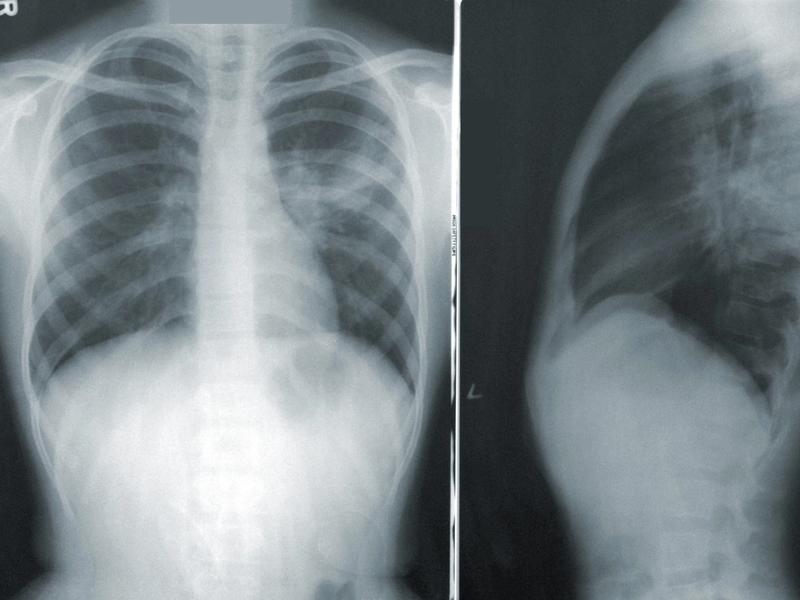

Po dotarciu do pediatry, lekarz zazwyczaj sugeruje kilka badań, aby dokonać trafnej diagnozy. Oczywiście, w grę wchodzi osłuchiwaniu klatki piersiowej, a czasami także RTG, chociaż coraz częściej zastępuje je USG. Warto być przygotowanym na to, że lekarz może zlecić dodatkowe badania laboratoryjne, które pomogą określić, czy w organizmie malucha znajdują się bakterie, wirusy czy inne patogeny. Im szybciej postawimy diagnozę, tym prędzej dzieciak wróci do pełni sił, co stanowi naszą główną misję!

Pediatra to prawdziwy superbohater w białym fartuchu, który potrafi skutecznie zdiagnozować przyczyny problemów zdrowotnych malucha. Dzięki starannemu wywiadowi medycznemu oraz badaniu fizykalnemu, lekarz precyzyjnie oceni sytuację, która zachodzi w płucach. W niektórych przypadkach konieczne będą dodatkowe badania, takie jak RTG – nie martw się, to nie jest czarodziejskie zaklęcie, lecz kluczowy krok w procesie leczenia! Zrozumienie, jaki typ zapalenia występuje – bakteryjny, wirusowy czy może grzybiczy – umożliwi wdrożenie odpowiedniej terapii, co przyspieszy powrót dziecka do zdrowia.